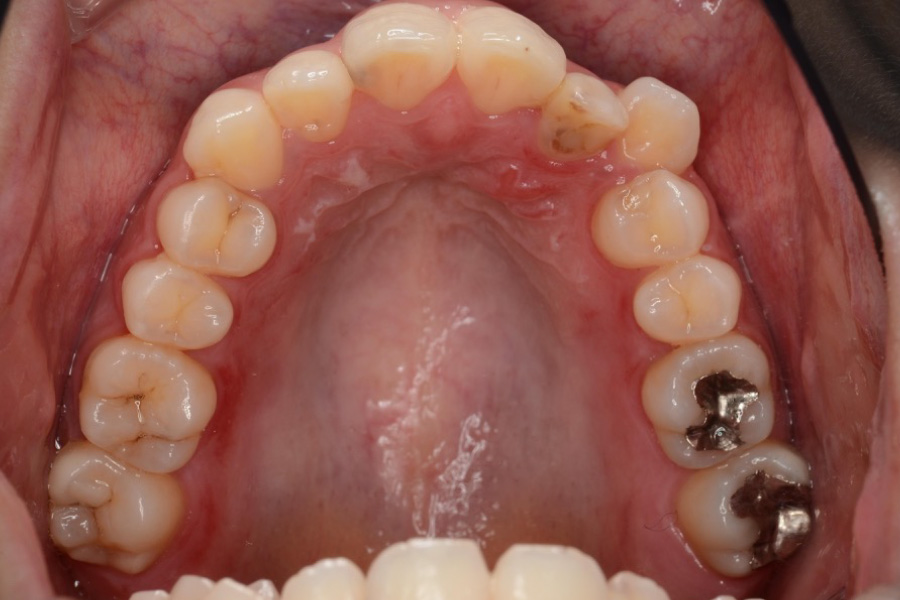

【30代女性】八重歯を

インビザライン矯正で治療したケース

治療前

主訴 八重歯

期間 2年半

費用 220,000円〜660,000円

(デンタルローン 3,100〜6,600円/月)

治療内容 インビザライン矯正

非抜歯